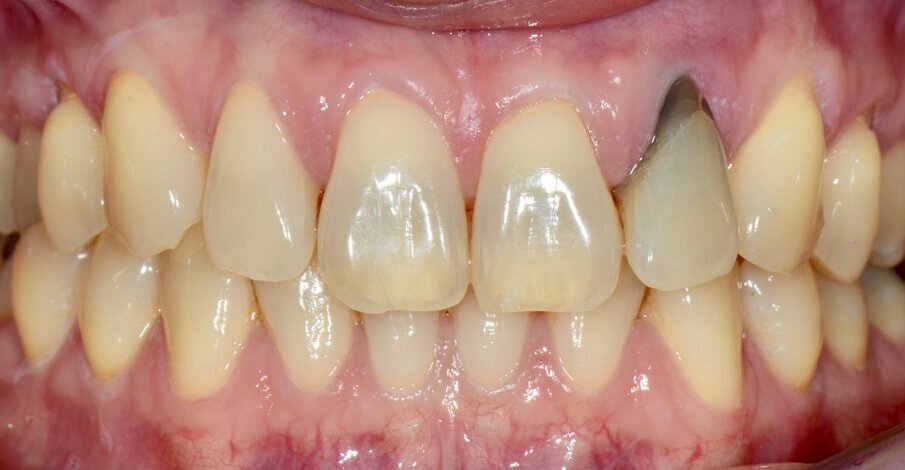

Six months of healing was necessary (Fig. 14) before unscrewing the provisional restoration, taking impressions and placing the definitive screw-retained crown on to the implant. Predictable aesthetic and functional results can be obtained using the technique described (Fig. 15); therefore, a rough clinical case study should always be conducted prior to any case in order to ensure atraumatic extraction and placement of implants and bone substitute in the optimal position.

Fig. 14: The six-month post-op examination revealed healthy tissue and an aesthetic outcome.

Figs. 15a & b: Pre-op (a) and post-op clinical views (b) showing an aesthetic result and healthy periodontal tissue.